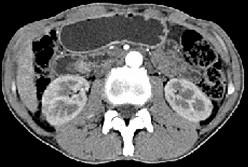

问题 男,48岁,进行性黄疸,发热,腹胀,影像检查如图,最佳的诊断是 ( )

选项 A、十二指肠乳头癌 B、胰头癌 C、胆总管结石 D、胆总管癌 E、胆总管囊肿

答案 A